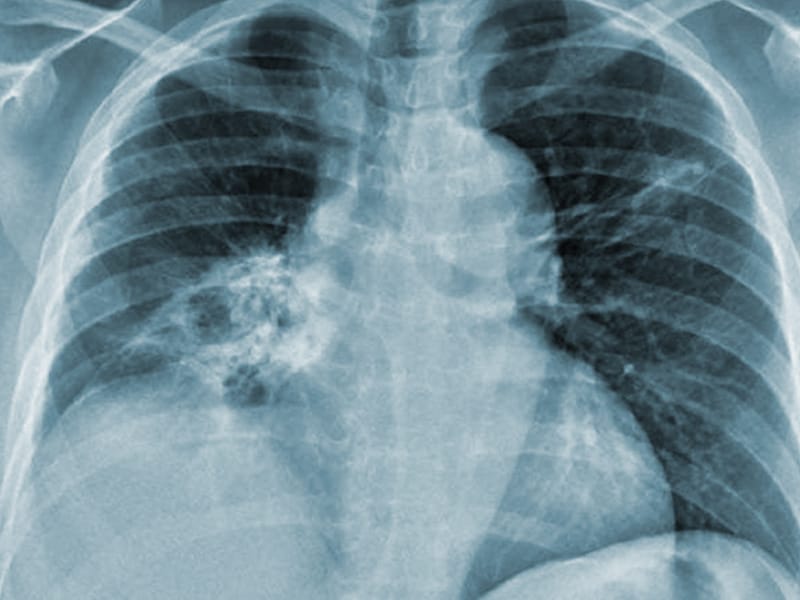

An example of a chest Xray and its corresponding radiology report in... Download Scientific